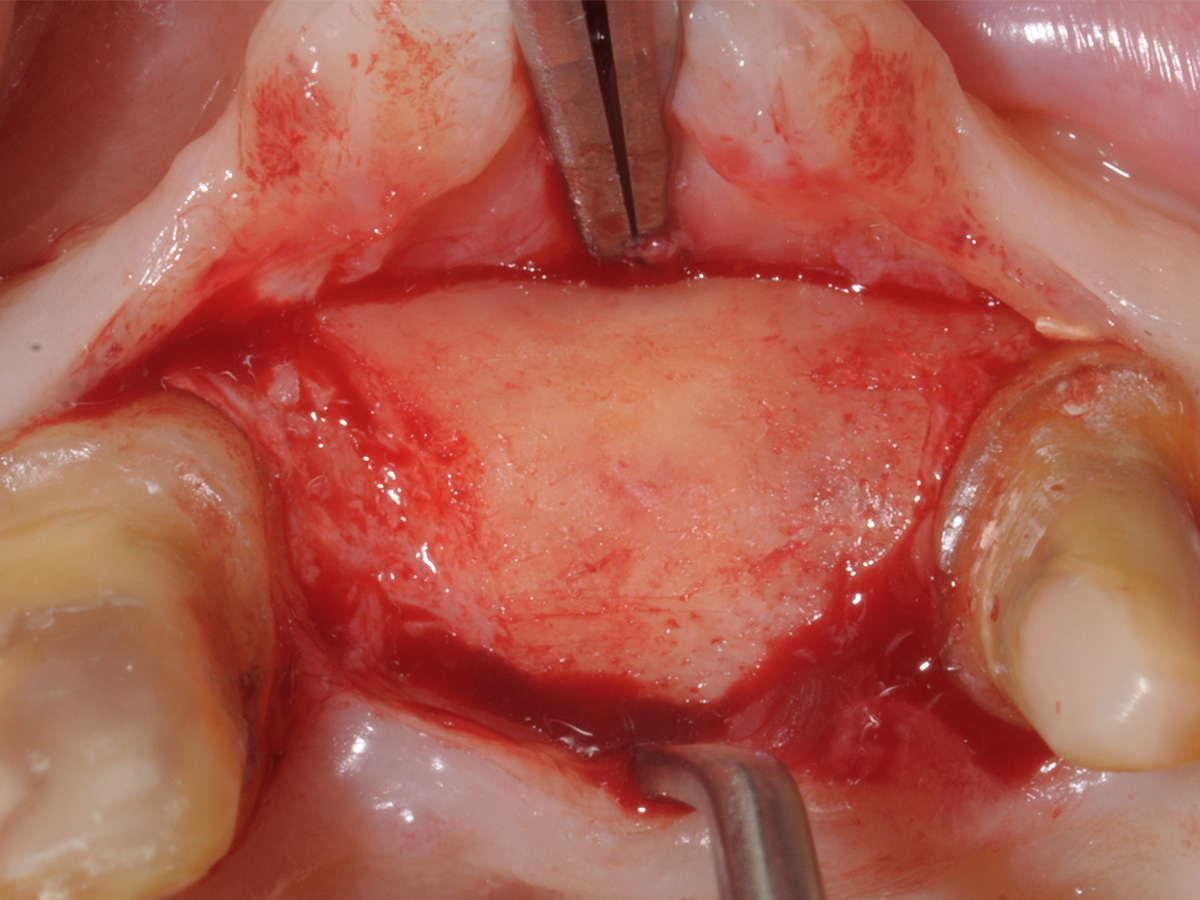

Abbildung 7

Abbildung 8

Aufbau mit OsteoBiol® mp3, Bone Lamina Soft und Evolution.